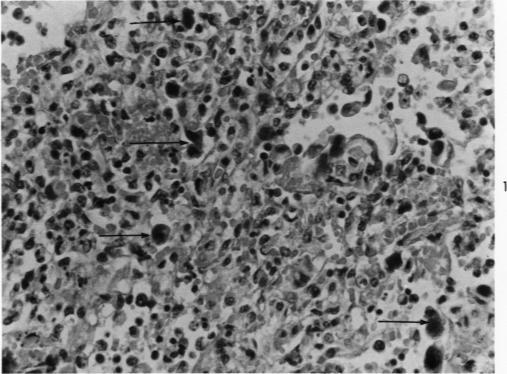

Many structures morphologically identical with adenovirions were found in large numbers in typically altered respiratory epithelial cells in 10-year-old sections stained with hematoxylin and eosin of 2 cases of a histologically unique type of fatal pneumonia in infancy. These observations confirm, beyond reasonable doubt, an etiologic role of adenoviruses in the initiation and development of this type of pneumonia. The technic used, which was a modification of one previously described, is given in detail, since such methods may be useful in solving other etiologic problems.